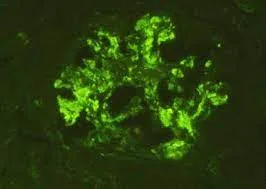

Idoso com GNRP, qual seria sua principal hipótese diagnóstica?

Idoso com GNRP, qual seria sua principal hipótese diagnóstica?Caso típico de GNRP em paciente idosos. Vendo a imagem, qual seria sua primeira hipótese diagnóstica?